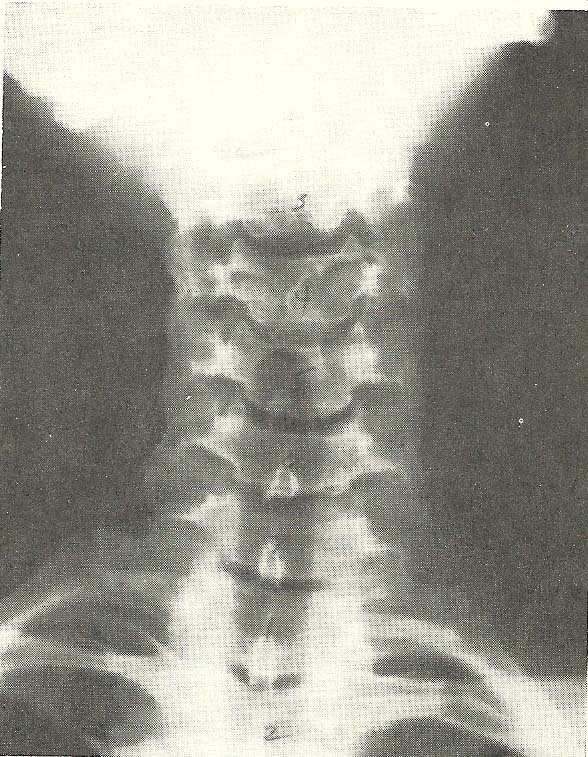

Case Illustrating Classifications A-1, A-3, A-4, A-8, and A-9

The x-ray views presented next are those of a 69-year-old female (Figs.

6.60--6.62). There is foraminal narrowing at four levels on the right and two

on the left due to proliferative changes (A-9). Flexion subluxation exists at

C4 (A-1), and marked interspace narrowing is found at C5, C6, and C7 (A-8). A

loss of normal cervical lordosis is evident. Rotary subluxation is present at

C2 and C3 (A-4). Also note the generalized osteoporosis.